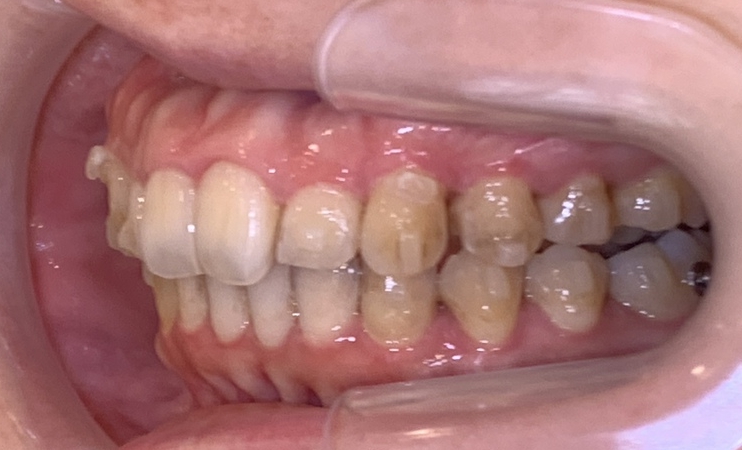

こちらがカウンセリング時のお写真です。

患者様のどこが気になっている部分か分かりますか?

抜歯は極力したくないという患者様で、スペースを取るために歯を多く削られてしまっています。

前歯を見るとよくわかりますよね?

↑左側で噛むことが出来ないという状態で、噛み合わせのズレが気になります。

そこで、再度、当院でマウスピースの治療をされています。

お口元を少しでも引っ込ませるために遠心移動(奥に歯をおくる)を行いながら噛み合わせの確立を行っています。